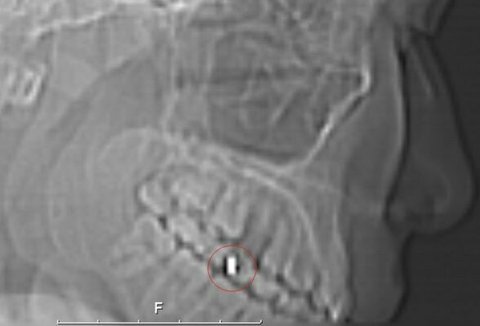

치과에서 임플란트 시술후

마인드컨트롤전파무기피해가

시작되서 임플란트를 뽑아 속을 보니 RFID칩이 발견되어 법정승소하는데 ~결정적인 증거로 작용되었다!